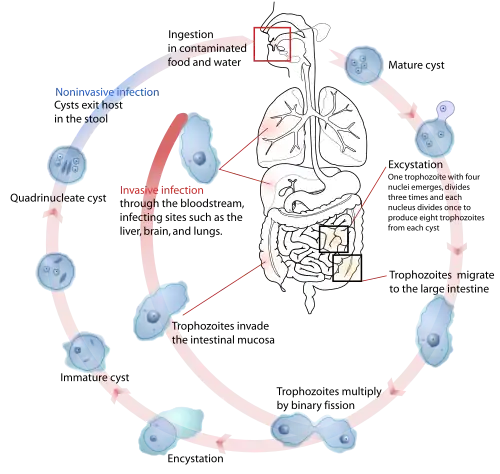

Lebenszyklus

Diese Organismen gelangen zumeist als Zysten mit verunreinigter flüssiger oder fester Nahrung über den oberen Verdauungstrakt in den Dünndarm des Wirtsorganismus. Hier entschlüpft der Zystenhülle ein vierkerniges Zellstadium, aus dem durch mehrfache Teilung dann acht kleine einkernige Trophozoiten von E. histolytica hervorgehen, die den Dickdarm besiedeln. Diese bilden in den meisten Fällen eine Kommensale mit dem Wirt.[2] Die Trophozoiten können sich durch binäre Zellteilung vermehren. Sie können auch Zysten bilden, die den Darm mit den Faeces verlassen. Bei massivem Befall kann die Ausscheidungsmenge durchaus 100 Millionen[3] Zysten pro Tag betragen.